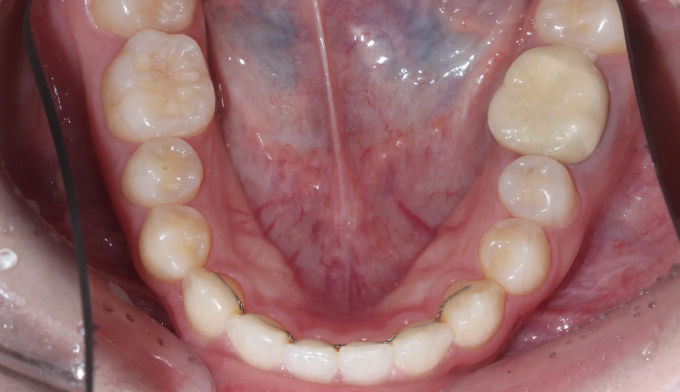

앞니 하나만 뒤로 들어간 경우, 해당 치아만 앞으로 빼내면 되는 간단한 교정이라고 생각하기 쉽습니다.

하지만 해당 치아가 뒤로 들어가면서 전체적인 치열이 한쪽으로 쏠리는 비대칭이 나타났기 때문에 이를 모두 해결하기 위해서는 전체교정을 통한 긴 치료기간이 필요합니다.

안쪽으로 들어간 앞니 양쪽으로 치열을 밀어서 공간을 확보해주고 앞니를 재위치 시켰습니다.

추가로 한쪽으로 틀어진 치열들도 위아래 중심선을 맞추어주었습니다.

총 치료기간은 17개월입니다.